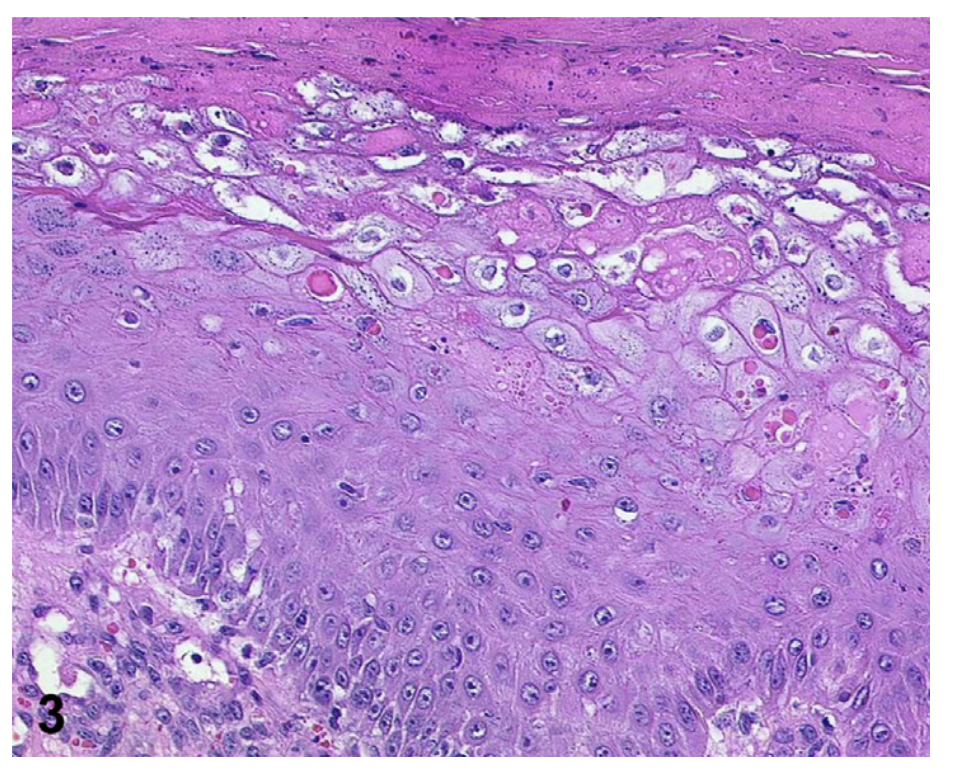

Histopathology of Monkeypox (Orthopox virus)?

Ballooning degeneration of keratinocytes with the presence of eosinophilic intracytoplasmatic inclusion bodies (Guarnieri bodies) is consistent with infection from Orthopox virus.

Dermoscopy with the trizonal pattern of central necrosis, white peripheral halo, and a paler pink zone has been also described as a reproducible and additional supportive tool to integrate clinico- pathological correlation when dealing with lesions potentially related to monkeypox.